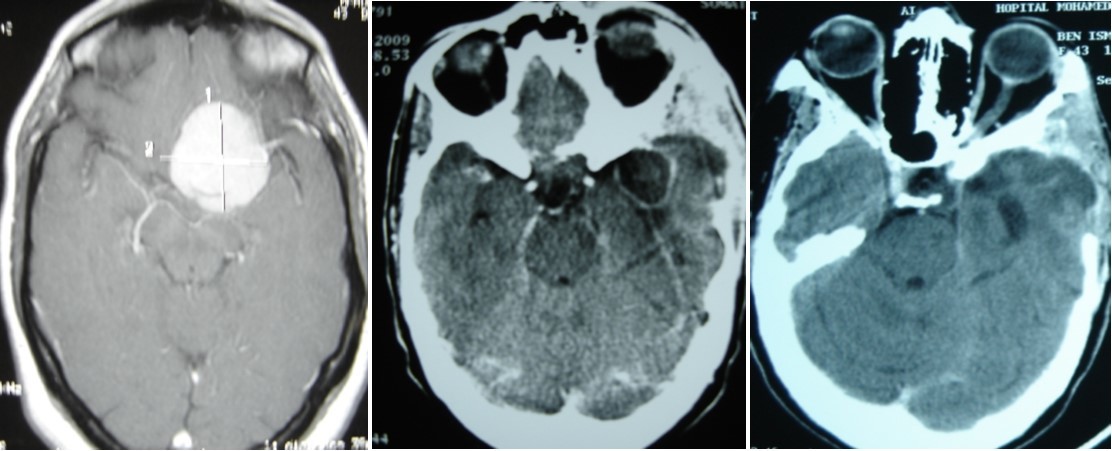

A 45 year-old woman, operated 6 months before for left sphenoid wing meningoma revealed by raised intracranial pressure, with hemiplegia. She underwent surgery, with simpson I resection. The post operative outcome was good and the patient was discharge. Six months later, she presented a swelling on surgical site of skin incision. Blood check found inflammation with raised C-Reactive Protein. CT scan permitted to suggest brain abcess and she was operated in emergency with bone flap removal and the abscess complete excision. Bacteriologic and Histologic examination of the pus, revealed aspergillus flavius. The patient was treated by amphotéricin B because it was the antifungal avalailable in the hospital officine. Two months treatment was necessary to controle cerebral aspergillosis (Figure 7) and the patient was discharged with good outcome.

Figure 7.(A) pre operative MRI, axial T1 weighted with enhancement of sphenoid wing meningioma. (B) Ct scan showing an brain abscess in post op area. (C) CT scan after remoral sugery and 2 months medical treatment.